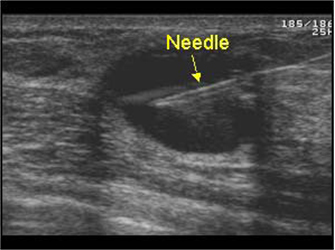

ε) Για να πραγματοποιήσουμε επεμβατική πράξη, όπου καθοδηγούμε τη βελόνα με τους υπερήχους για βιοψία συμπαγούς μορφώματος (εικόνα 4) ή εκκένωση κύστης (εικόνες 5,6) ή τοποθέτηση συρμάτινου οδηγού σε ογκίδιο για την ακριβή εξαίρεσή του χειρουργικά.

(Εικόνα 4)

(Εικόνα 5)

(Εικόνα 6)